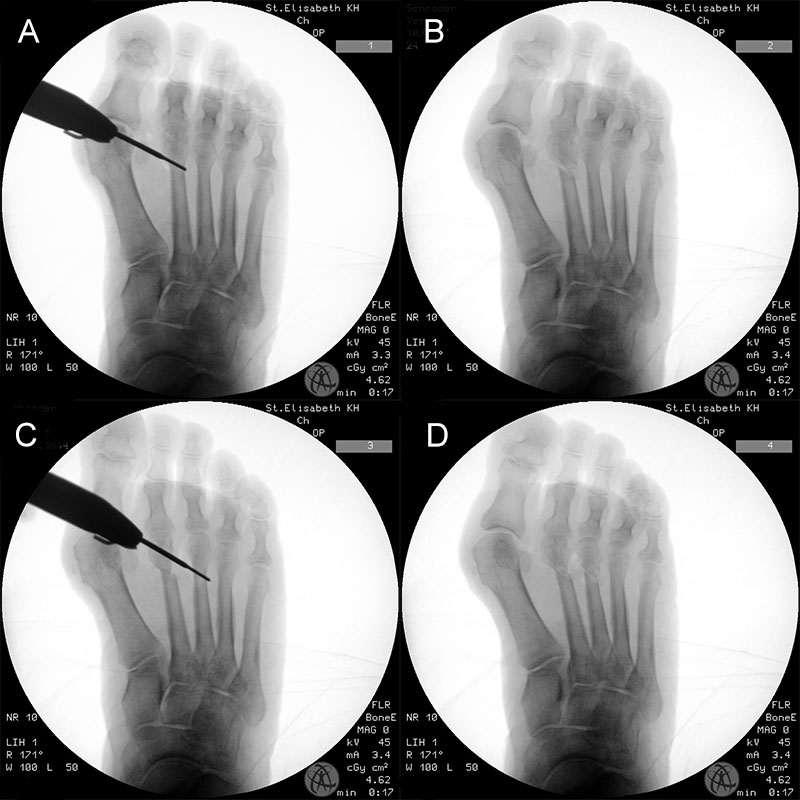

Das hier vorgestellte Konzept beruht auf den grundsätzlichen Überlegungen von Sharma, unter Anwendung der Prinzipien der minimalinvasiven Fußchirurgie. Die Korrektur der Adduktionsfehlstellung der Metatarsalia II bis IV erfolgt über eine modifizierte, lateralisierende, distale, minimalinvasive Metatarsale-Osteotomie (DMMO) (interner Link: OP Technik DMMO). Die Osteotomie der Metatarsalia II bis IV ohne Osteosynthese erlaubt eine limitierte Verlagerung der Metatarsaleköpfchen nach kranial, was ein etabliertes Verfahren zur Therapie einer Metatarsalgie darstellt 7. Eine zusätzliche, im Normalfall unerwünschte Lateralverschiebung der Metatarsaleköpfchen kann bei einem Pes adductus zur Korrektur genutzt werden. Verglichen zu offenen Therapieverfahren ermöglicht dieses Konzept die Korrektur der Adduktionsstellung der Metatarsalia II bis IV bei minimiertem Weichteiltrauma und verkürzter die OP-Dauer. Persönliche Erfahrungen mit dem Verfahren deuten darüber hinaus auf ein geringeres postoperatives Schmerzniveau, eine einfachere Mobilisierbarkeit und eine hohe kosmetische Zufriedenheit hin.

• Turbine für minimalinvasive Fußchirurgie (Drehzahl ca. 2000-5000 RPM und Drehmoment 80 N/cm).

• Konische Fräse (Wedge burr 13 mm / 4,3 mm Ø).

• Gerade Fräse (Straight burr 13mm / 2mm Ø) Shannon recta 2.0.

• BV für intraoperative Kontrollaufnahme.

Zum Lesen der Bildbeschreibung und zur Vollansicht bitte die Bilder anklicken.